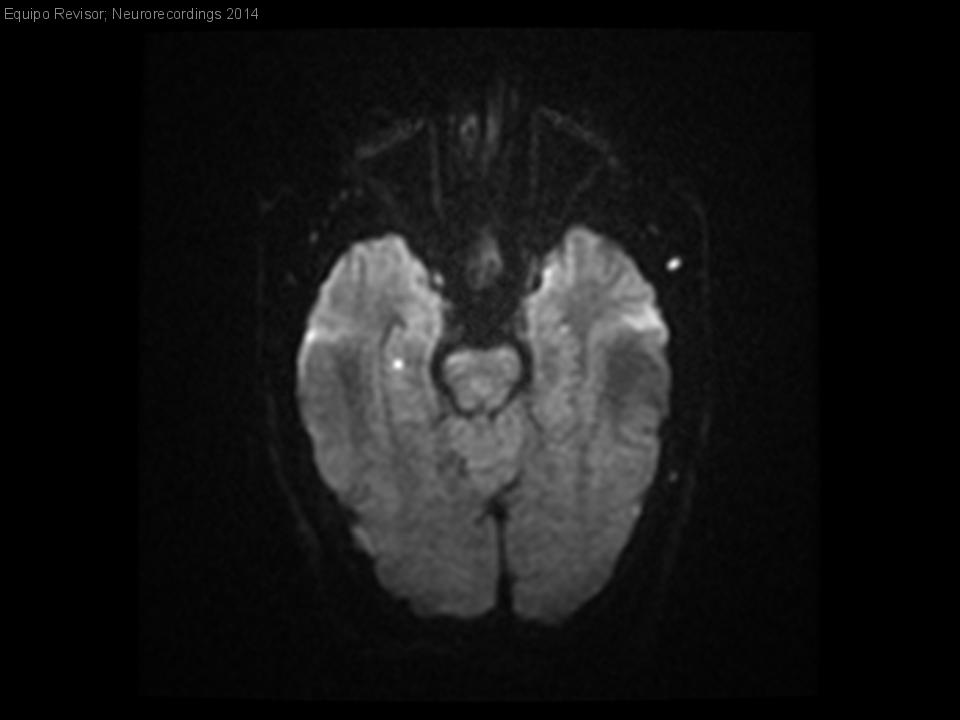

Diagnóstico final: Amnesia global transitoria